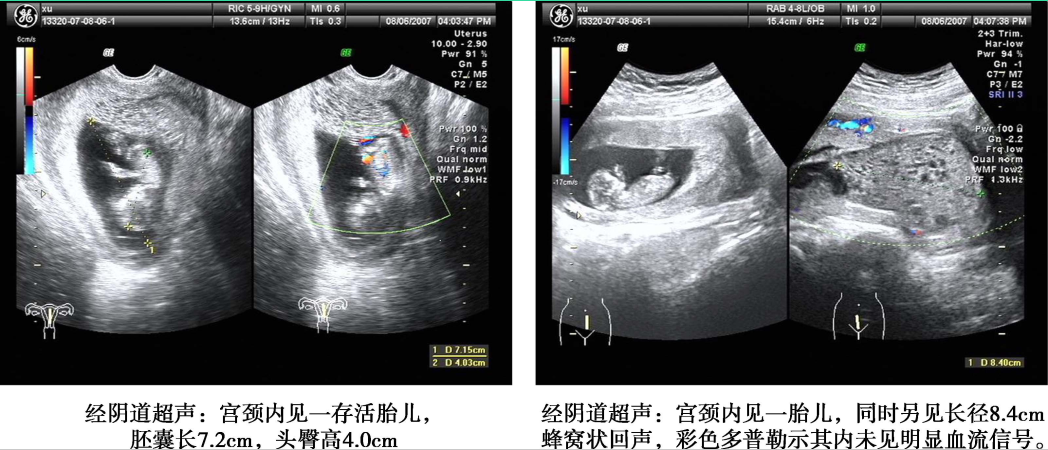

1.超声检查 是常用的辅助检查,最好采用经阴道彩色多普勒超声。完全性葡萄胎的典型超声图像为子官大于相应孕周,无妊娠囊或胎心搏动,宫腔内充满不均质密集状或短条状回声,呈“落雪状”,水泡较大时则呈“蜂窝状”。常可测到双側或一侧卵巢囊肿。彩色多普勒超声检查可见子宫动脉血流丰富,但子宫肌层内无血流或仅稀疏血流信号。部分性葡萄胎可在胎盘部位出现由局灶性水泡状胎块引起的超声图像改变,有时还可见胎儿或羊膜腔,胎儿通常畸形。早期葡萄胎妊娠的超声征象常不典型,容易误诊。

部分性葡萄胎超声影像(患者A)

部分性葡萄胎超声影像(患者B)